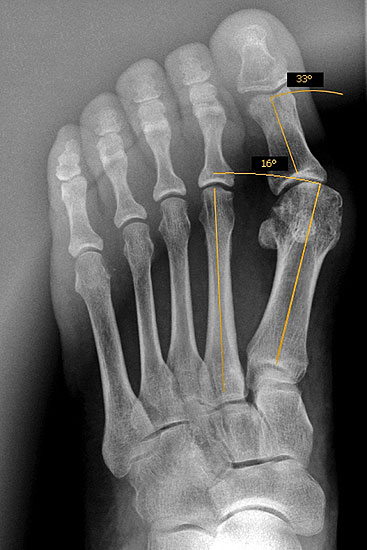

Abbildung 1

Klinische Untersuchung des gesamten Fußes unter Entlastung und Belastung

Röntgenaufnahmen des Fußes d.p., streng seitlich und schräg unter Belastung

Operationsplanung anhand der Röntgenaufnahmen unter Beachtung wichtiger radiologischer Landmarks wie Intermetatarsalwinkel, Hallux valgus – Winkel, Distaler Gelenkflächenwinkel (Distal metatarsal articular angulation: DMAA), Metatarsaleindex und Sesambeinposition (Abbildung 1)

Die Chevron Osteotomie ist eine der weltweit am häufigsten angewandten Verfahren zur Korrektur einer milden bis mittelgradigen Valgusfehlstellung der Großzehe 1110121319148. Die zahlreichen Publikationen berichten über relativ verlässlich gute und reproduzierbare Ergebnisse. Durch Modifikationen in der Operationstechnik versuchten einige Autoren den Indikationsbereich auf mittelgradige bis schwerwiegende Fehlstellungen auszuweiten 121314. Die Bestimmung des Schweregrades der Fehlstellung erfolgt in erster Linie am belasteten Röntgenbild im dorsoplantaren Stahlengang (siehe Abbildung 1). An dieser Aufnahme können die wichtigsten radiologischen Vermessungen zur Operationsplanung vollzogen werden 112310121312728172930, auch wenn in einigen Studien eine große inter- und intraindividuelle Schwankungsbreite der Messergebisse dargestellt werden konnte 2930. Ebenso zeigt sich eine gewisse Varianz in der Methodik zur Bestimmung des ersten Intermetatarsalwinkels 18282931. Als Grenzwerte für einen milden bis mittelgradigen Hallux valgus werden in der Literatur in relativ weiter Übereinstimmung ein Intermetatarsalwinkel bis maximal 16° und ein Hallux valgus Winkel bis 40° genannt 688. Der DMAA ist radiologisch schwierig zu beurteilen und sollte intraoperativ bei Gelenkeröffnung inspektorisch überprüft werden 2. 2007 verglichen Trnka et al. (2007) die Ergebnisse von vier verschiedenen Nachuntersuchungsgruppen, die sich durch Modifikationen der OP Technik unterschieden: 66 Chevron Operationen von 1991 bis 1992, 100 Chevron Operationen von 1992 bis 1995, 55 Chevron Operationen von 1994 bis 1995 und 89 Chevron Operationen von 2000 bis 2002. So wurde der dorsomediale Zugang 1992 durch einen streng medialen Zugang mit L-förmiger Kapsulotomie ersetzt. 1992 wurde das laterale Release über einen dorsalen Zugang eingeführt mit Perforation der lateralen Kapsel längs zwischen Metatarsale 1 und fibularem Sesambein, sowie vertikal im Verlauf der Gelenklinie ohne Ablösung des Adduktors oder Durchtrennung des intermetatarsalen Bandes. Zwischen 1994 und 2000 wurde eine temporäre Fixation mit einem Kirschnerdraht durchgeführt. Seit 2000 wird die Osteotomie mit einer kanülierten Kompressionsschraube fixiert. Insbesondere die Einführung des lateralen Release führte zu einer signifikanten Verbesserung des Hallux valgus- und Intermetatarsalwinkels, ohne vermehrt Probleme mit einer avaskulären Nekrose des MTK 1 zu bekommen. Die Einführung einer Osteosynthese mittels Kirschnerdraht zeigte im follow up nach 34 Monaten gegenüber der lediglich manuellen Einstauchung des distalen Fragments, wie in der Originalarbeit von Austin beschrieben, eine geringere Rate an Korrekturverlusten und Dislokationen des ersten Metatarsaleköpfchens. Durch die Verwendung einer Schraube konnte das Indikationsspektrum hinsichtlich Schweregrad des Hallux valgus erweitert werden. Der Vergleich einer 2-Jahres- und eines 5-Jahres-Nachuntersuchung zeigte gegenüber der präoperativen Untersuchung eine Verbesserung des IM-Winkels von 13° auf 8° respektive 9°. Der HV-Winkel konnte von durchschnittlich 29° auf 15° respektive 16° reduziert werden. Ergebnisse, welche auch die langfristige Zuverlässigkeit der Chevron-Osteotomie in der Behandlung des milden bis mittelgradigen Hallux valgus belegen.